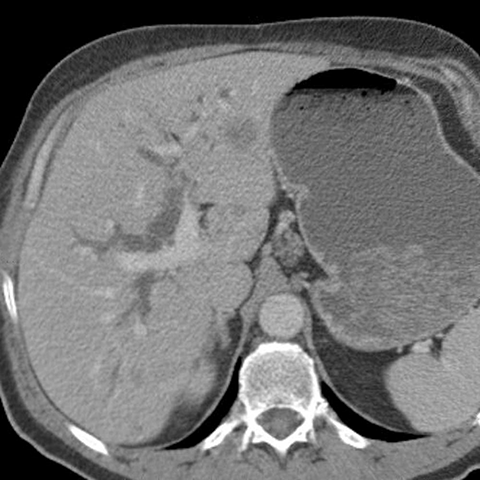

56 year-old male presents with painless jaundice [1 of 7]